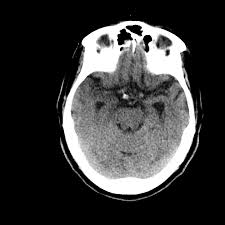

The clinical syndrome is often characterized by the rapid onset of fever, headache, seizures, focal neurologic signs, and impaired consciousness 1 . Two subtypes are recognised which differ in demographics, virus, and pattern of involvement. Hatipoglu hg(1), sakman b, yuksel e. On pathology, herpes viruses cause a fulminant hemorrhagic and necrotizing meningoencephalitis, with typical gross findings of severe edema and massive tissue necrosis, with petechial hemorrhages. The patients with the former type of lesions had fulminating disease, and were in severe clinical condition.

Watershed distribution ischemia in areas remote from the primary herpetic lesions may be seen. Normal mr imaging findings (type 1, 53% of patients), isolated hippocampal involvement (type 2, 13%), other brain lesions without hippocampal involvement (type 3, 13%), and other brain lesions with hippocampal involvement (type 4, 21%). On pathology, herpes viruses cause a fulminant hemorrhagic and necrotizing meningoencephalitis, with typical gross findings of severe edema and massive tissue necrosis, with petechial hemorrhages. For viral infection of the meninges, please refer to the general article on viral meningitis, and, for a broad view on the curriculum of infections of the central nervous system, refer to cns. Therefore, recognition of the mr imaging. In their important analysis, the authors describe 4 distinct imaging patterns: Lesions similar to cytotoxic edema, and lesions similar to vasogenic edema. Hatipoglu hg(1), sakman b, yuksel e.

Lesions similar to cytotoxic edema, and lesions similar to vasogenic edema. Seizure, altered sensorium, fever frontal and temporal lobes, rarely extratemporal t2 hyperintensity, restricted diffusion, sometimes. Herpes encephalitis is the most common sporadic encephalitis in the united states and other industrialized countries .occurring as either a primary infection with herpes simplex virus or as a reactivation of latent virus, herpes encephalitis causes significant morbidity and mortality .early intervention with acyclovir significantly improves outcome; The clinical syndrome is often characterized by the rapid onset of fever, headache, seizures, focal neurologic signs, and impaired consciousness 1 . Having said that, mri with contrast is considered the most sensitive imaging modality, and findings are present in over half of individuals 8. The patients with the former type of lesions had fulminating disease, and were in severe clinical condition. Herpes simplex encephalitis occurs as 2 distinct entities: 4 it was found that, rather surprisingly, varicella zoster virus (vzv), the cause of chickenpox and herpes zoster, was the most frequently detected virus at 29%, with hsv and enteroviruses accounting for 11% of cases. Two subtypes are recognized which differ in demographics, virus, and pattern of involvement. (1)department of radiology, ankara numune education and research hospital, ankara, turkey. Neonatal herpes simplex encephalitis is caused by vertical transmission of infection during passage from birth canal with diffuse cerebral involvement within the first month after birth; As the older term limbic encephalitis implies, the most common location of involvement is the mesial temporal lobes and limbic systems, typically manifested by cortical thickening and increased t2/flair. In patients with herpes encephalitis, two distinct types of diffusion imaging findings (on b =1000 s/mm 2 images, and adc maps) were noted: